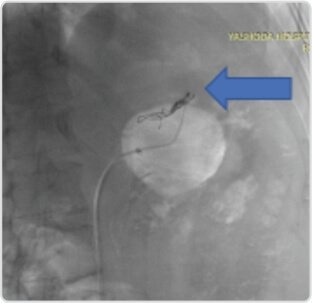

Complete occlusion of aneurysm after deployment of amplatzer vascular plug (arrow) in proximal splenic artery